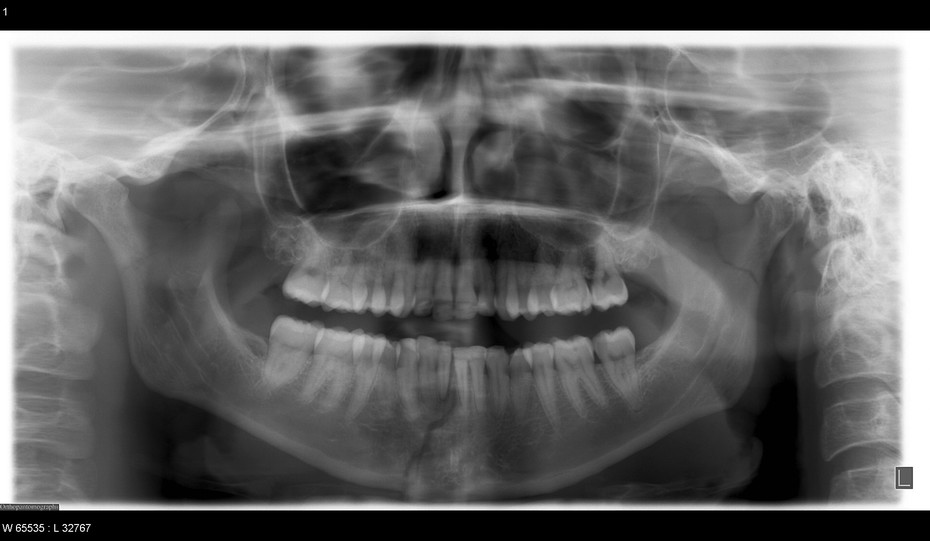

Mandible Fracture X Ray View . After the nasal bones, the mandible is considered the second most common site of facial fractures. Physical assault) and motor vehicle collisions. Etiology and demographics will vary significantly. Mandibular fractures the mandible is another commonly fractured bone in the head, and most of these fractures are obvious on clinical exam. When plain films are used to diagnose mandibular fractures, one should include radiographs taken in two planes at 90° to each other. Both views are necessary because fractures are often only seen on one image. In patients with traumatic injury of the mandible. The minimum requirement is a pa view and a panoramic view. Orthopantomogram (opg) and mandible views.

Orthopantomogram (opg) and mandible views. Mandibular fractures the mandible is another commonly fractured bone in the head, and most of these fractures are obvious on clinical exam. In patients with traumatic injury of the mandible. The minimum requirement is a pa view and a panoramic view. When plain films are used to diagnose mandibular fractures, one should include radiographs taken in two planes at 90° to each other. After the nasal bones, the mandible is considered the second most common site of facial fractures. Physical assault) and motor vehicle collisions. Both views are necessary because fractures are often only seen on one image. Etiology and demographics will vary significantly.